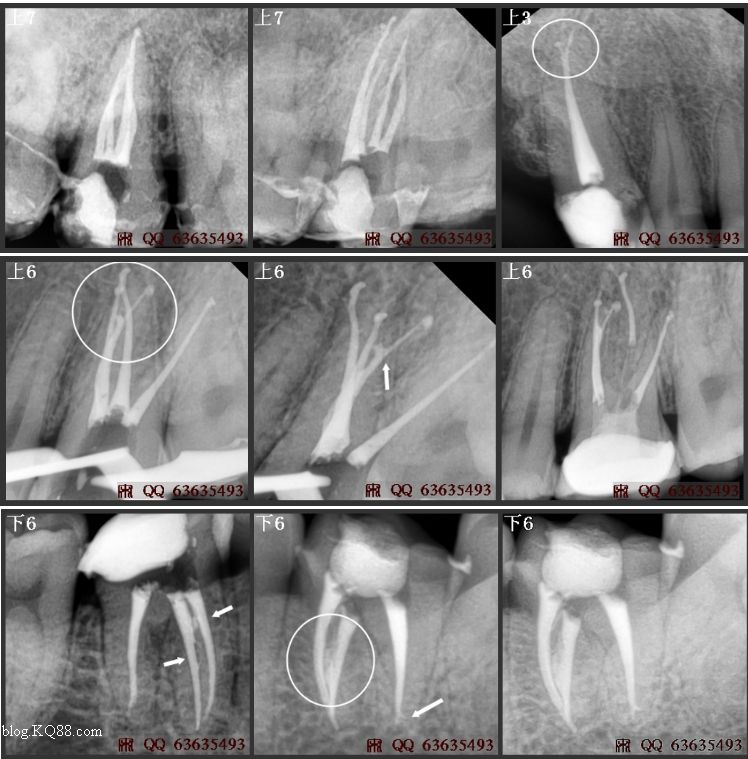

成人恒牙有28~32顆(如圖01),第一磨牙,它是體積較大、牙根和根管解剖最復(fù)雜的;“六齡牙”也是最常需要治療而被了解的又最少的后牙。它的根管治療失敗率較高,但毫無疑問它是最重要的牙齒之一(如圖02/03/34)。

根管口永遠(yuǎn)位于顏色較暗的髓室底和顏色較淺的髓室壁的交界處,且通常處在暗色底線角的頂點(diǎn)上(如圖09/16)。直到暗色髓室底和淺色髓室壁的交界清晰可見,通路預(yù)備才算充分。如果看不清楚這一交界,說明髓室頂還沒有被全部磨除。

上頜磨牙髓腔形態(tài)和根管位置見圖14,臨床病例見圖(16…29/33/34)。上頜第一磨牙一般9~10歲時(shí)根尖形成,平均長(zhǎng)度為20.8mm。上頜第二磨牙一般14~16歲時(shí)根尖形成,平均長(zhǎng)度為20.0mm。80%的上頜磨牙根尖孔至根尖的距離在1mm以內(nèi)。

上六的3個(gè)牙根可向不同的方向發(fā)生彎曲:55%的腭根頰向彎曲,78%的近中根管彎向遠(yuǎn)中,19%的遠(yuǎn)中根彎向近中。詳見圖表15

老版的教科書記載上頜磨牙通常為3個(gè)牙根和3個(gè)根管,近來很多資料表明上頜第一磨牙存在4個(gè)根管的比例大于70%,用放大鏡或手術(shù)顯微鏡放大以尋找額外根管,MB2發(fā)現(xiàn)率為90%以上(如圖27/29/33/34)。作為施術(shù)者心中不了解牙齒,根管治療中遺漏根管,就根本談不上根管治療的成功。(詳見本文開頭部分)